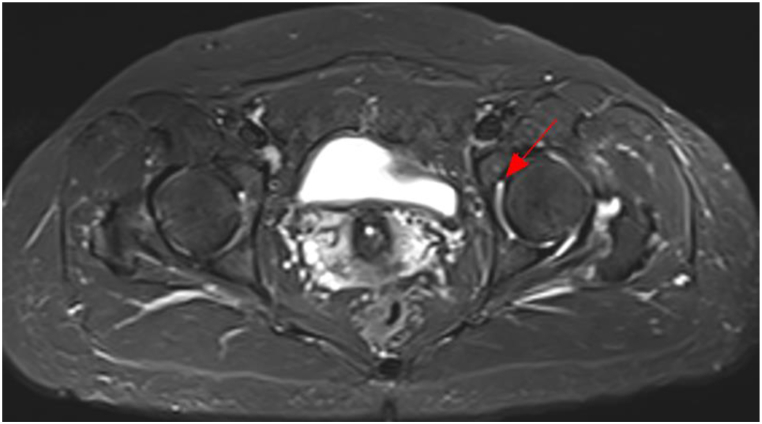

Following a diagnosis of pneumonia caused by TW infection, a treatment plan consisting of ceftriaxone followed by compound sulfamethoxazole was formulated for Patient 3. However, the patient refused intravenous ceftriaxone and was discharged from the hospital. Subsequently, Patient 3 changed to take TMP-SMZ orally. After twenty days, the patient developed gastrointestinal reactions, and discontinued taking the medicine independently. Despite no significant change (Fig. 3(a and b)) indicated by chest CT scan one year later, Patient 3 experienced intermittent cough, recurrent joint pain and diarrhea, and reported joint pain on September 7, 2022. MRI examination of both hips revealed a small amount of fluid in the left hip joint of this patient (Fig. 4).

Fig. 4.

MRI of both hips of Patient 3. The arrowhead shows the focus.

Notably, the treatment of WD in patients with respiratory symptoms as the principal complaint remains in its incipient stages, and the treatment plans implemented by clinicians are far from standardized [5]. In our study, Patient 1 was subjected to a rigorous and intensive analysis via mNGS, and the subsequent results of this analysis were utilized to tailor the treatment regime to more effectively target the underlying pathogen. Ultimately, remarkable improvement was achieved in the condition of Patient 1. Conversely, Patient 2 demonstrated notable improvement after receiving empirical treatment with piperacillin-tazobactam. Despite our provision of a standardized treatment plan, Patient 2 adamantly refused to follow the scheme. Similarly, Patient 3 refused the administration of intravenous ceftriaxone on account of personal reasons, and instead received TMP-SMZ. Upon discontinuation of treatment, the patient evinced the reappearance of joint pain and sporadic diarrhea. Notably, one year subsequent to the cessation of treatment, re-examination of chest CT scans in this patient indicated no appreciable improvement in lung lesions, while hip MRI indicated the presence of effusion in the left hip joint. Our supposition is that this poor prognosis can be attributed to the patient's failure to receive an effective and standardized course of anti-TW infection treatment. This failure resulted in the persistence of lung lesions, which in turn accelerated the involvement of extrapulmonary organs such as the gastrointestinal tract and bones and joints, leading to recurrent joint pain and intermittent diarrhea. Tragically, Patient 4 died suddenly before receiving proper and standardized treatment. Patient 5 did not undergo the standard WD treatment regime due to the inadequate experience and training of the attending physician in the diagnosis and treatment of pneumonia caused by TW infection.